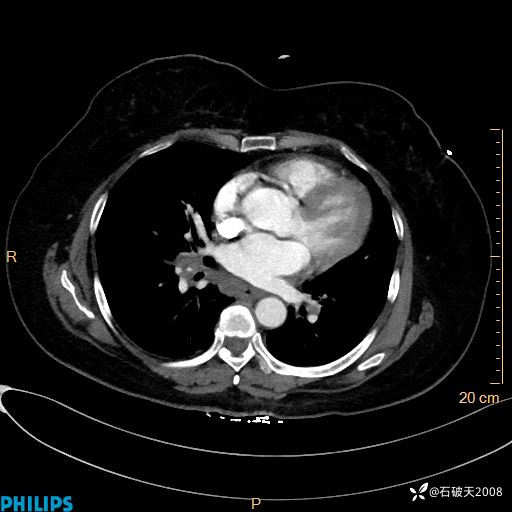

肺结节病?纵膈型肺癌?淋巴瘤?有点意思,欢迎围观

女 52岁 主 诉:咳嗽10余天,咳痰2天。

现病史:10余天前无明显诱因出现咳嗽,呈阵发性干咳,伴咽喉部发痒,无咽痛,无咳痰,无鼻塞、流涕、打喷嚏,无发热、畏寒、寒颤,无头痛、头晕,无胸闷、胸痛,无反酸、烧心,无腹痛、腹泻,无尿频、尿急,无皮疹等,在当地诊所求治,给予口服药物治疗(具体不详),病情无好转。遂在当地社区卫生服务中心开具口服药物治疗(具体不详),疗效欠佳。2天前出现咳痰,在我院门诊求治,行胸部CT提示肺部感染,建议住院,患者要求口服药物治疗,目前仍咳嗽、咳白色粘痰,白天量多,夜间自觉喉部喘鸣音,遂再次来院就诊,以“肺部感染”为诊断收入院。发病以来,神志清,精神可,饮食可,夜间睡眠差,大小便正常,近期体重无明显变化。

动脉期